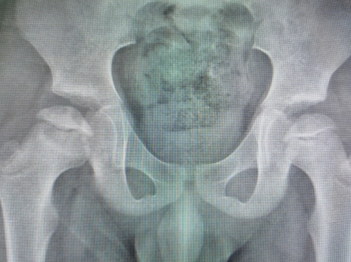

术后X线

目前,几位患儿经过手术治疗均已顺利出院。

“股骨头缺血坏死”这种疾病一般发现确诊时就要诊治,症状表现为髋关节压痛明显,被动内旋时疼痛明显,X线的变化主要是干骺端、骺板及髋臼的改变,可能发现股骨头变形,核磁共振对于股骨头内、外侧显影更为清晰。治疗方式早期一般有卧床休息、牵引治疗、双下肢内旋位管型石膏固定,后期为恢复股骨头血供,使股骨头形态发育正常,可选择股骨头钻孔引流、髂腰肌松解术来治疗。